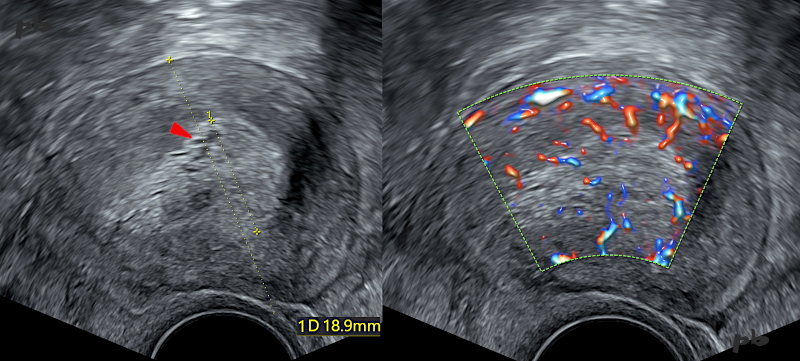

3 – Endometrial Hypertrophy

Sagittal view via endovaginal ultrasound. Metrorrhagia in the perimenopausal period under progestin therapy.

Left image:

* Thickened endometrium (18.9 mm between the crosses).

* Homogeneous echotexture, with rare hypoechoic oval images (►): glands.

* The cavity is not individualized.

* The interface with the myometrium is sharp and regular.

Right image: Multiple vascular flows, evenly distributed.

Conclusion: Thickening without suspicious imaging signs. Dilation and curettage performed. Histology reveals glandular-cystic atrophy of the endometrium. A thickened endometrium on imaging can correspond to histological atrophy. This is a classic scenario with tamoxifen (see further details later).